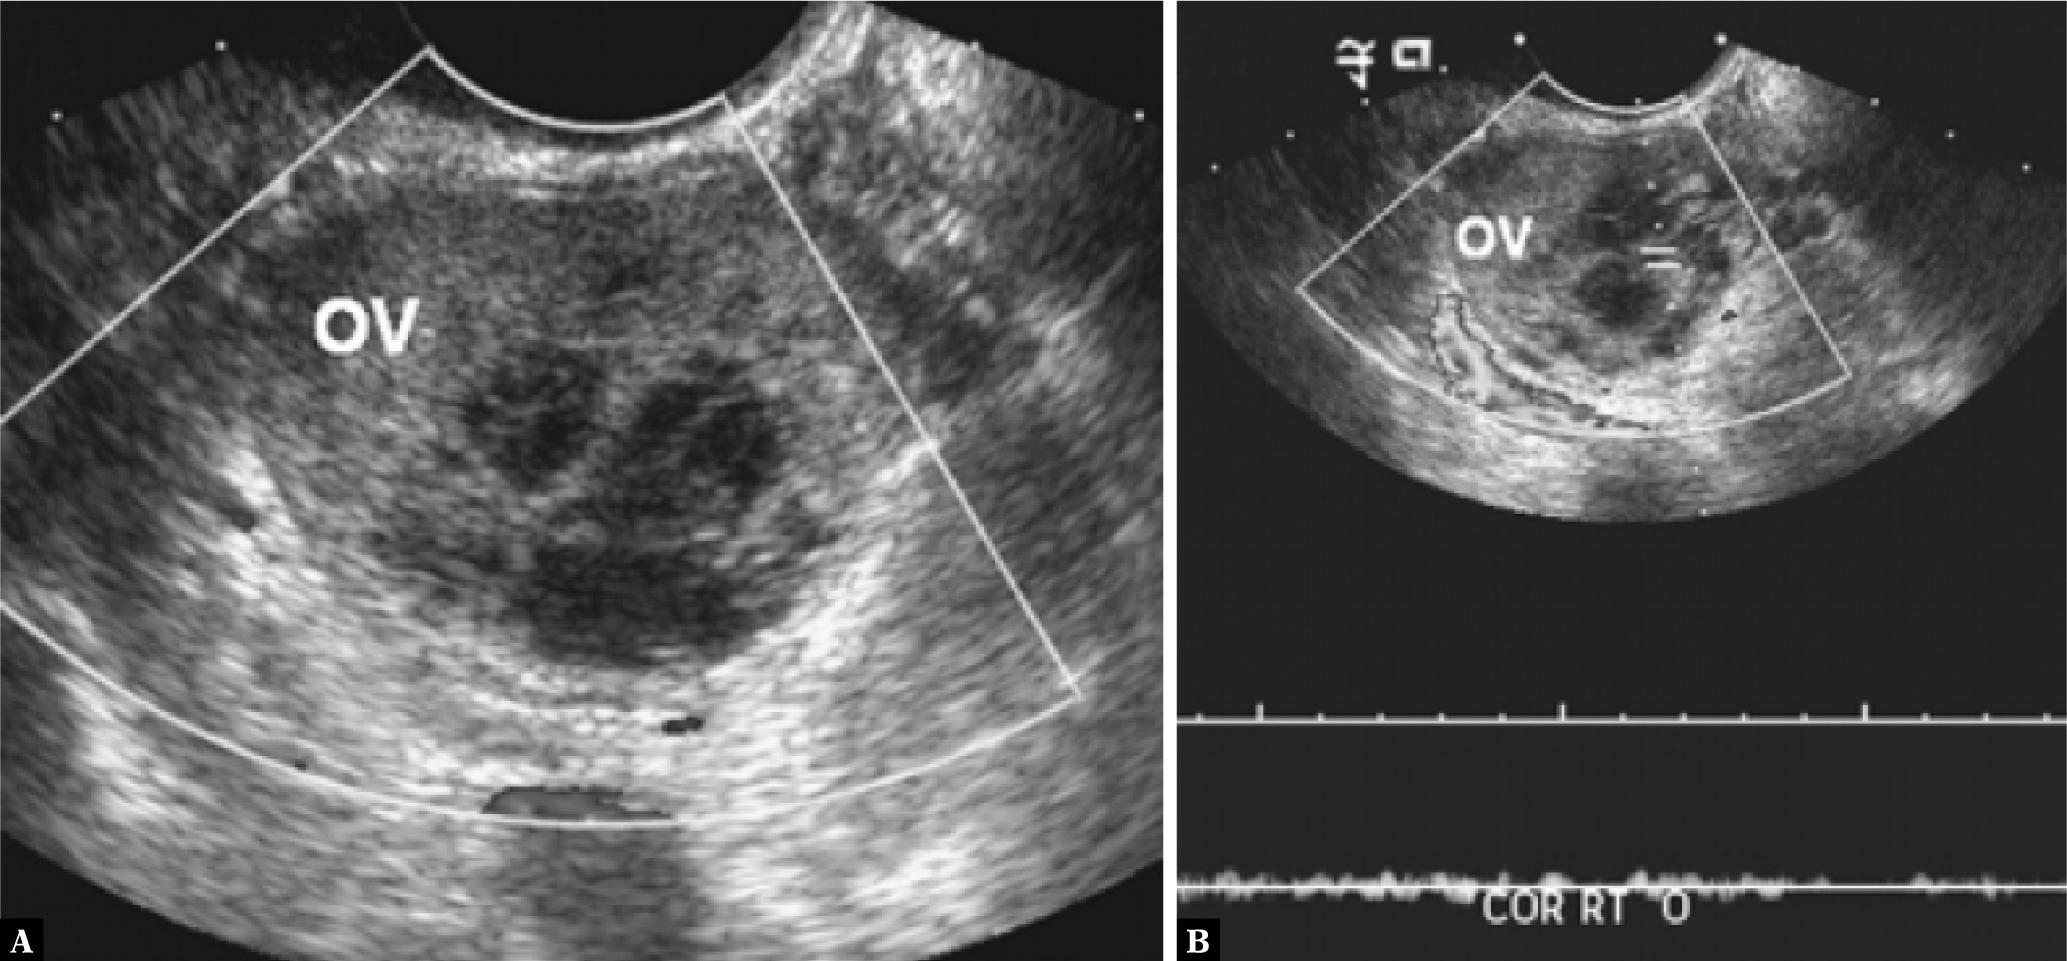

Fig. 3.